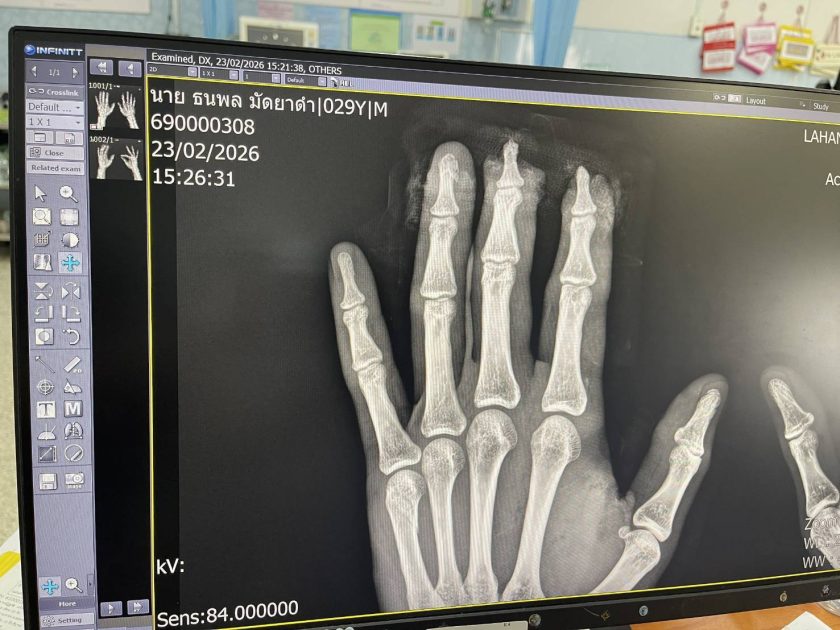

กองทัพภาคที่ 1 เปิดเผยว่า ทหารสังกัดกองทัพภาคที่ 1 ถูกสะเก็ดระเบิดได้รับบาดเจ็บ ขณะปฏิบัติหน้าที่ลาดตระเวนบริเวณจุดตรวจหลักเขต 28 พื้นที่รอยต่อตาพระยา–ละหานทราย บริเวณผาหินตัด ชายแดนรอยต่อ จ.สระแก้ว และ จ.บุรีรัมย์ ต่อมาทราบชื่อ ผู้ได้รับบาดเจ็บ คือ ส.อ.ธนพล มัดยาดำ ตำแหน่งพลลาดตระเวน สังกัดกองร้อยลาดตระเวนระยะไกลที่ 2 กองพลทหารราบที่ 2 รักษาพระองค์ ถูกสะเก็ดระเบิดบริเวณฝ่ามือซ้าย ปลายนิ้วชี้ และนิ้วกลางขาด ขณะนี้ได้รับการผ่าตัดพ้นขีดอันตรายแล้ว